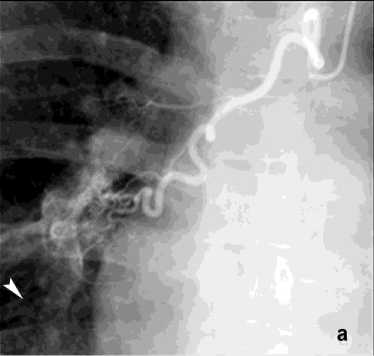

Первым этапом в процессе диагностики бронхоскопии через фибробронхоскоп выполняли промывание трахеи холодным физиологическим раствором, инъекции адреналина (рис. 5). При наличии и доступности определённого источника кровотечения использована электрокоагуляция с ис- сечением опухоли бронха 4 (2,7%), бужирование и стентирование бронха 11 (7,3%). При интенсивном кровотечении в 13 (8,7%) случаях выполняли брон-хоблокацию. Удаление блокатора осуществляли на 5–8 сутки. В одном случае бронхоблокация сочеталась со стентированием аорты. Проведённый анализ ангиограмм позволил выявить косвенные признаки ЛК. В большинстве случаев наблюдалось усиление кровоснабжения зоны поражения независимо от выявленной патологии (рис. 6, а). Локализация сосудистых изменений соответствовала данным, полученным при таких диагностических методах как ФБС и КТ. Эти ангиографические признаки не имеют прямого отношения к ЛК, но достаточно полно характеризуют его причину в силу специфичности семиотики различных лёгочных заболеваний. Прямые признаки экстравазации мы наблюдали в одном случае при наличии аортобронхиального свища (рис. 9, а).

Рецидив ЛК после эмболизации наблюдался у 15 (10%) пациентов, в 3 случаях из них эмболизация БА была выполнена более года назад. В результате ангиографического поиска выявлены дополнительные источники ЛК: межреберные артерии – 4, внутренняя грудная артерия – 8 (рис. 8), АV – 3 (рис. 7).

Рисунок 8. Ангиограмма правой внутренней грудной артерии (ПВГА) у пациента с ЛК 2А, клапанная эндоблокация): а – гиперваскуляризация нижней доли правого легкого; б – состояние после эмболизации ПВГА микроэмболами (710–1000 мкм ) – заполнение только ствола ПВГА

Figure 8. Angiogram of the right internal thoracic artery (RITA) in a patient with PH grade 2A (valve endobronchial occlusion): a – hypervascularization of the lower lobe of the right lung; б – status post embolization of the RITA with microembolic particles (710–1000 μm) – filling of the RITA trunk only